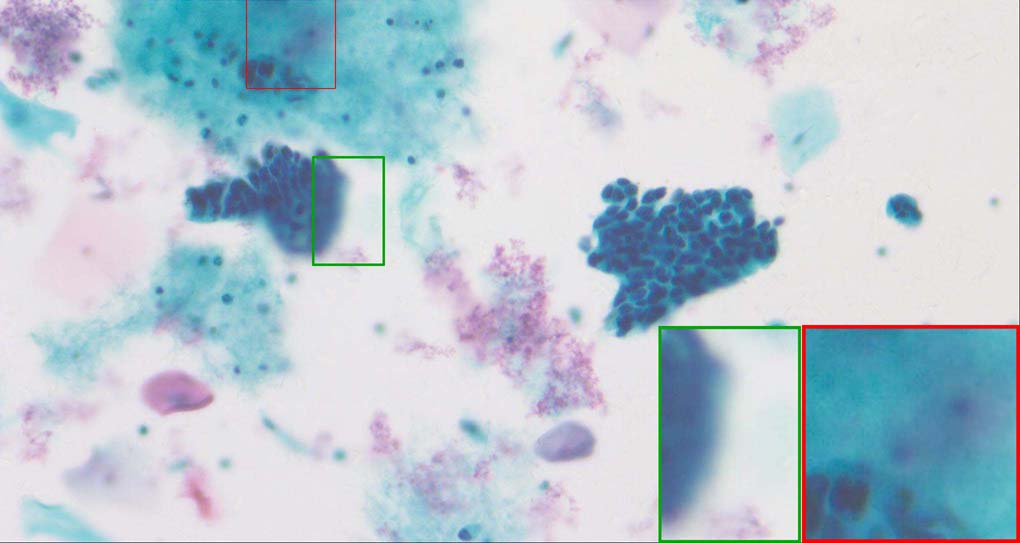

Pixel-level image fusion intends to combine different images of the same scene by mathematical techniques in order to create a single composite image that will be more comprehensive and thus, more useful for human or machine perception [1, 2]. For instance, multi-modal image fusion [3] tries to fuse images which have been acquired via different sensor modalities exhibiting diverse characteristics for a more reliable and accurate medical diagnosis. Another typical application is the multi-focus image fusion [4]. As the depth-of-field (DoF) of bright-field microscopy is only about 1~2 micrometers, while the specimen’s profile covers a much larger range and then the parts of the specimen that lie outside the object plane are blurred. The multi-focus image fusion can obtain an all-in-focus image from multiple images taken under different distance from the object to the lens of the identical view point.

A good image fusion method should contain the following properties. First, it preserves both the details of small size objects and the integrity information of large size objects in the fused image, even in the case of the size of the interested objects varying largely in the image. For example, the cervical cell images from the microscope contain both small size isolated cells and large size agglomerates, which are both useful for cervical cytology [5]. Second, it should be efficient enough to handle large-scale data. For instance, it needs to process thousands of fields of view (FoV) in an acceptable time for the whole slide scanning in digital cytopathology [6], which requires to fuse a series of high resolution images captured at each FoV in a very efficient way. Third, it does not produce obvious artifacts. Despite being studied extensively, to our best knowledge, existing fusion methods may not meet these requirements simultaneously.

To demonstrate the effectiveness and efficiency of the proposed image fusion method , we conduct a set of comparative experiments on three image datasets. The first is composed by 8 pairs of multi-modal medical images and the second one contains 15 pairs of multi-focus gray or color natural images. These two datasets are often used in many related papers and some examples are shown in Figure 3(a) and Figure 3(b). The third one is a new multi-focus cervical cell image dataset collected by ourselves, which consists of 15 groups of color images and each group contains a series of multi-focus cervix cell images with size of or , etc. Some source examples are shown in Figure 3(c). Our source code implemented in C++ along with the new multi-focus cervical cell image dataset is available online.

Figure 9, Figure 10 and Figure 11 show the comparative fused results of the multi-focus cell images shown in Figure 3(c). For clarity, we also present a closeup view in the right-bottom of each sub-picture in Figure 9 and Figure 10. As shown in the close-up views of Figure 9, the fused images based on DSIFT, IM, MWGF and BF methods are extremely blurred in the boundary and fail to keep the details of cell nucleus. Furthermore, the DTCWT and NSCT based methods produce halo artifacts in the fused images, while GFF and CNN based methods fail to preserve the small cell nucleus. LP-SR based method nearly works fine which keeps the most of the details of the small size cells, but the integrity of the clustered large size cells is damaged. Fortunately, in our proposed method, the integrity of the clustered large size cells is preserved and most of the isolated small size cells are maintained from the original images, which demonstrates the best visual quality.

Similarly, as shown in the close-up views of Figure 10, the fused images from DSIFT, IM, MWGF and BF are blurred and lose some nucleus details, while the results from DTCWT, GFF, CNN and NSCT produce halo artifacts. LP-SR based method can keep details well but also produces halo artifacts and other noise. Our method can preserve the focused areas of different source images well without introducing any artifacts. For the example illustrated in Figure 11, the fused images generated by DSIFT, DTCWT, IM and NSCT all fail to preserve the focused areas of different source images and result in extremely blurred images. The GFF, CNN, MWGF and BF based method introduces a lot of color distortion of the nucleus regions and the obvious halo artifact. The result of LP-SR based method is close to the one of our method but introduces some odd color distortion. Again, our method produces fused image which can preserve the focused areas of different source images well without introducing any artifacts.